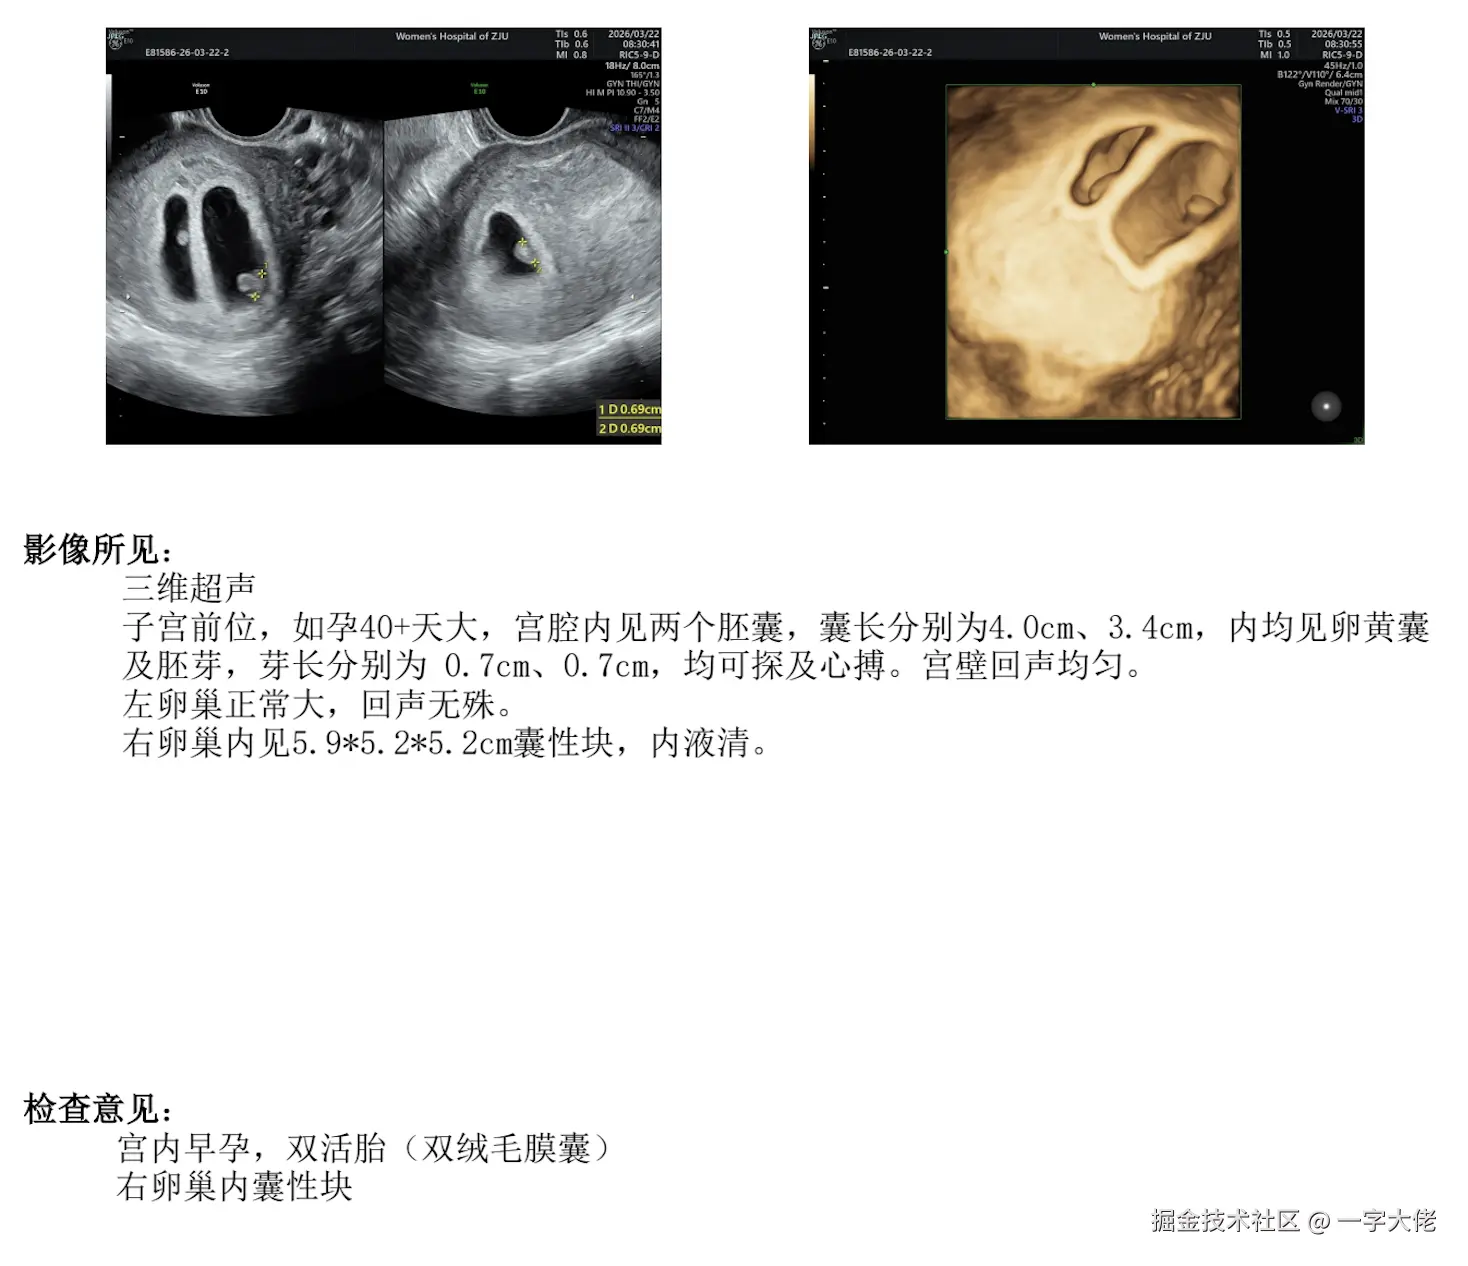

老婆怀孕6周了 上周突然发现大姨妈没来 然后去医院抽血测出来的 很惊喜!老婆现在待业在家,我每天早上7点多起来做早饭+准备零食水果+中午的菜(主食老婆自己搞定,现在孕吐很严重,主要还是得休息),然后晚上7点到家准备晚饭,这几天都是下班忙到9 10点然后就洗澡睡觉了。托宝宝的福我们现在都不熬夜了[哭笑][哭笑] 目前感觉有点小累 但是很充实 下周末去社区医院做b超看胎心胎芽 感觉生活一下就有了目标和动力 加油!!!